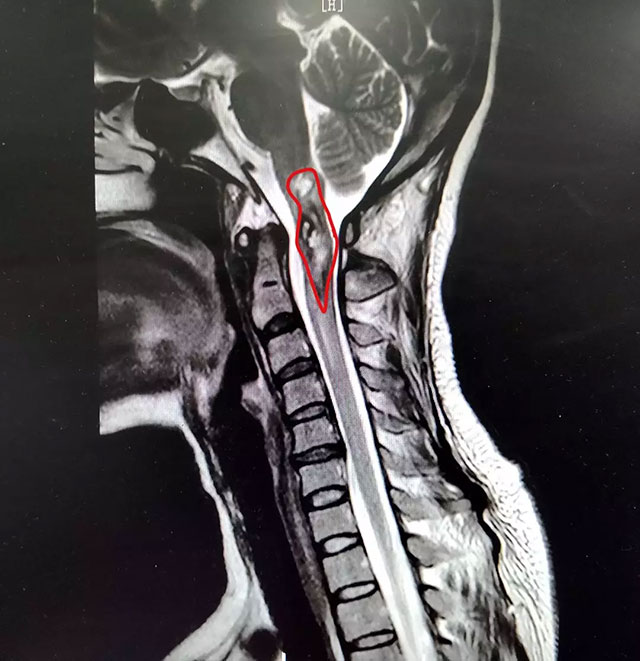

▲ 潘仁龙主任指出患者病灶位置

在患者身体条件允许的情况下,通过对患者进行选择性脊髓血管造影检查,明确诊断其延髓-颈2位置的占位病变为海绵状血管瘤伴脊髓空洞症。

▲ 经过治疗,患者脊髓内出血得到控制

姜女士患上的海绵状血管瘤,是隐匿性脊髓血管畸形的一种。虽然普遍认为这是一种良性肿瘤,但由其并发髓内出血时,会导致神经功能障碍。潘仁龙主任表示,由于这一部位的手术难度较大、风险很高,结合患者实际状况和本人意愿,决定对其采取对症保守治疗方案,以期让患者减轻症状,尽可能恢复活动能力。